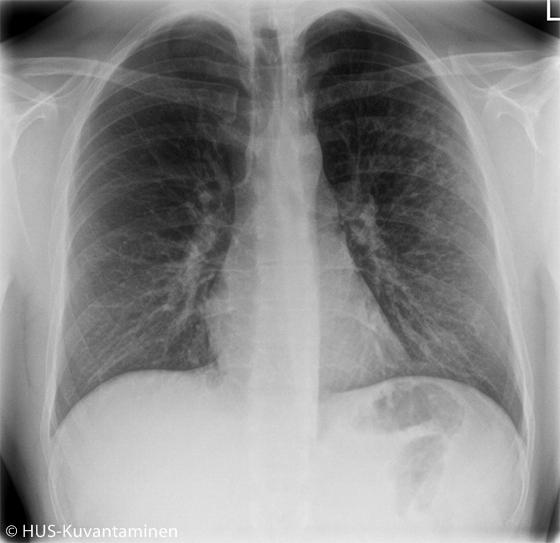

Atypical pneumonia in a patient with HIV (radiograph without markers).

A young man had been coughing and experiencing low-grade fever for 2 weeks. The patient had HIV, which had been managed appropriately. Obstruction was heard in pulmonary auscultation.